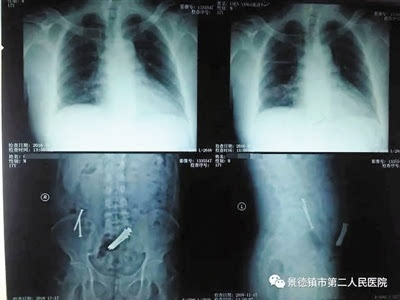

彭飞听后给“少年”做了检查,发现其小肠内确实有9枚长达6厘米的长钉,所幸钉子并未划破肠道。经过医生会诊及进一步的全面检查,医院决定为“少年”暂行保守治疗,先通过进食韭菜、金针菇等粗纤维食物包裹钉子保护肠道,然后喝石蜡油促进钉子的排出。

11月22日,“少年”顺利排出3枚长钉,两天后,又排出了其余6长钉。钉子排出后,此人除了大便血外,其他方面并无大碍。